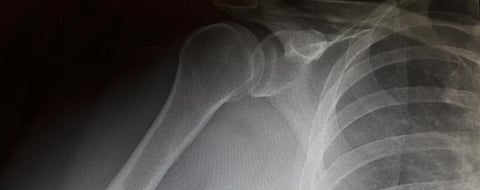

A research paper from the Penn School of Dental Medicine in the United States has shown that a new “plant-grown protein drug” may be a boon for those suffering bone fractures. The drug — that uses the protein ‘insulin-like growth factor-1’ (IGF-1) — stimulates growth of bone-building cells and promotes bone regeneration, according to the study.

The finding may prove to be beneficial for those who have diabetes, as they are more susceptible to bone fractures. Diabetes patients also take longer than usual to heal from such injuries.

The researchers thus targeted the IGF-1, important for bone and muscle health. Those who have lower levels of IGF-1 in blood are prone to an increased risk of breaking bones.

Diabetes patients “tend to have reduced bone repair and increased fracture risk, presenting a treatment challenge,” said Shuying (Sheri) Yang, the study’s co-author.